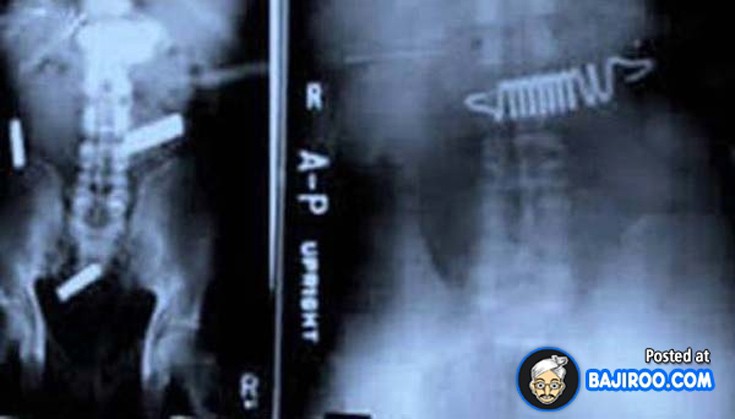

Ο,ΤΙ ΝΑ 'ΝΑΙ #ακτινογραφίες Παράξενα πράγματα που έχουν δείξει οι ακτινογραφίες Από δαχτυλίδια μέχρι πιρούνια και καρφιά - Δείτε τις φωτογραφίες 15·04·2016 11:08 1 σχόλια